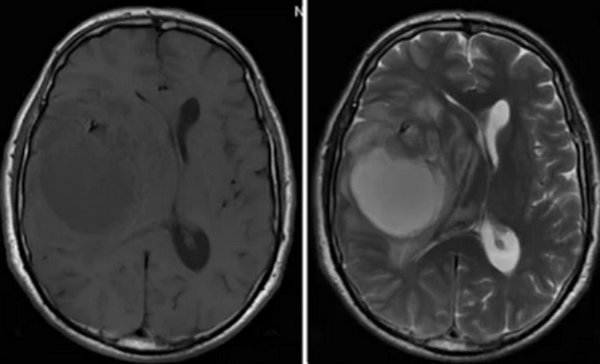

МРТ головного мозга выявляет скопление гемосидерина. Наиболее чувствительны градиентные Т2-взвешенные МРТ. Часто отмечается атрофия червя мозжечка, особенно, видимая хорошо на сагиттальных Т1-взвешенных МРТ.

При выявлении гемосидероза при МРТ в СПб мы (в том числе и на открытом МРТ в частном центре) ставим своей задачей поиск причины кровоизлияния. Дифференциальный диагноз при МРТ головного мозга проводится с меланозом и менингиоангиоматозом. Меланоз относится к факоматозам и обязательно сопровождается большим кожным невусом. Меланин сокращает релаксационные времена, что делает кровь светлой на Т1-взвешенных МРТ. Менингиоангиоматоз относится к редкому варианту сосудистых мальформаций и отличается локальностью поражения, мозг под ним также изменен в связи с сосудистой пролиферацией и фиброзом.

На МРТ классически выглядит как «обод» низкой интенсивности по поверхности головного или спинного мозга, что хорошо видно на последовательностях градиентного эха или SWI-последовательностях.

Для выявления поверхностного сидероза МРТ является методом выбора. Признаки весьма специфичные - мягкая мозговая оболочка и эпендимальная поверхность из-за скоплений гемосидерина имеют низкую интенсивность сигнала, особенно в области ствола мозга и мозжечка (червь и листки мозжечка - наилучшие места для выявления отложений). В давних случаях может наблюдаться атрофия мозжечка.

- Т2: снижение интенсивности;

- Т1: снижение интенсивности;

- Т2*: снижение интенсивности сигнала вплоть до его выпадения;

- SWI: снижение интенсивности сигнала вплоть до его выпадения;